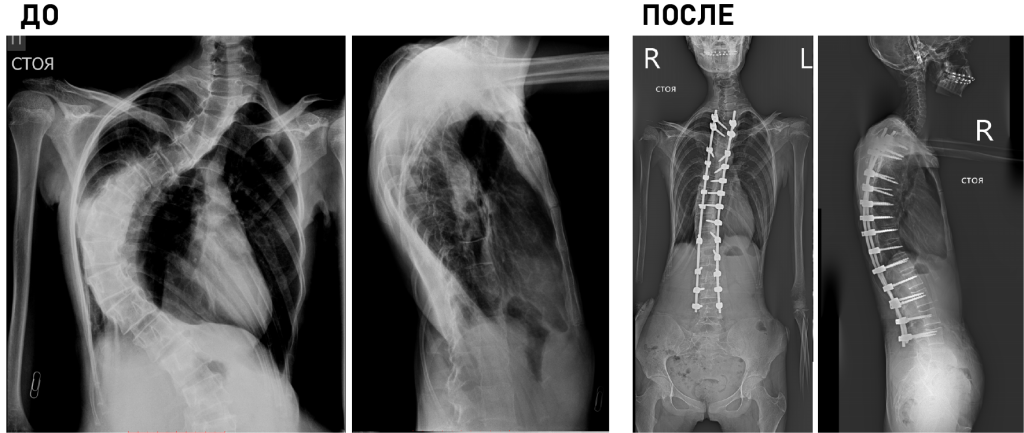

Клиника является единственным медицинским учреждением Российской Федерации, выполняющим полный комплекс диагностических и лечебных мероприятий у детей с деструктивными поражениями любых отделов скелета, в т.ч. малоинвазивные биопсии, иммунологические исследования, гистологическую и бактериологическую верификацию.

Основной принцип работы: обязательный учет возрастных особенностей ребенка и потенциал его роста.

Технические возможности: технологии малоинвазивной (MIS) и реконструктивной хирургии, костнопластические материалы и инструментальная фиксация, современное силовое и ультразвуковое операционное оборудование, навигация, нейромониторинг.